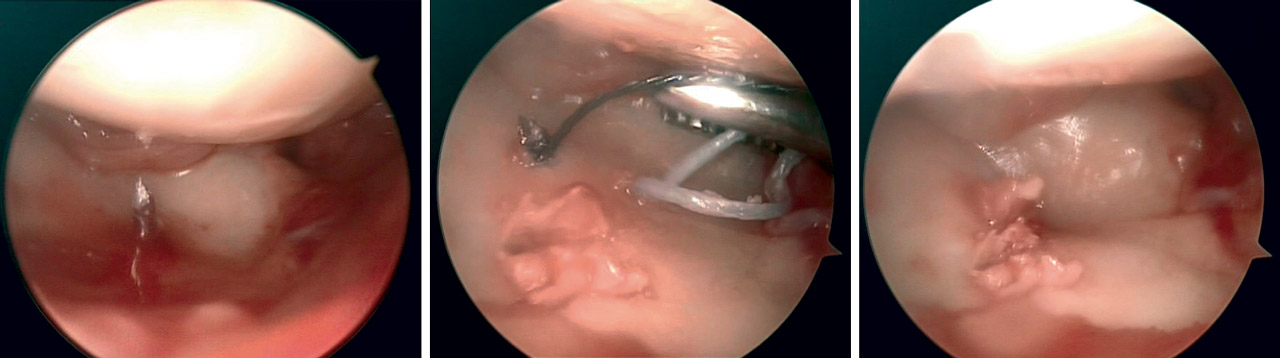

• En fracturas con componente principalmente articular se realiza artroscopia de inicio y la fijación de la fractura se efectúa visualizando directamente la reducción “fragmento a fragmento”, sosteniéndolos en empalizada con agujas de Kirschner (AK) o tornillos percutáneos, comprobando de forma directa la reducción de la superficie articular (Figura 5). No se realizó fijación con placa volar en estos casos.

El tratamiento de las lesiones asociadas fue realizado en función del grado y el tipo de lesión asociada (Figura 6), como se detalla a continuación.

Lesión del ligamento escafolunar

Se utilizó la clasificación de Geissler(6)(Tabla 1) para la toma de decisiones terapéuticas:

• Grado I: tratamiento conservador o retensado térmico.

• Grado II: retensado y fijación con tornillo a compresión escafosemilunar.

• Grado III: RAFI con anclaje-reparación ligamentosa y fijación con tornillo a compresión escafosemilunar (Figura 7).

• Grado IV: en los casos en los que encontramos ligamento con suficiente entidad, se realizó una reparación directa al igual que en el grado III. En caso contrario, se realizó una plastia mediante abordaje dorsal mínimamente invasivo con tendón palmar menor.

Los tornillos escafosemilunares se retiraron a los 4 meses de la cirugía.